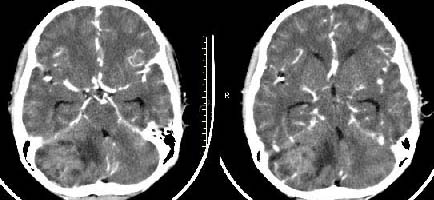

以下是引用子期在2009-6-10 21:34:00的发言:[br]髓母细胞瘤一般位于中线附近和小脑蚓部,该病灶位于右侧小脑半球,倾向于毛细胞型星形细胞瘤,当然也不能完全排除髓母细胞瘤。

以下是引用随光逐影在2009-6-10 22:26:00的发言:[br]考虑右侧小脑胶质瘤,髓母细胞瘤待排。

以下是引用影象小泰斗在2009-6-10 22:14:00的发言:[br]年龄及影像表现军符合小脑星形细胞瘤表现![br]期待病理结果!